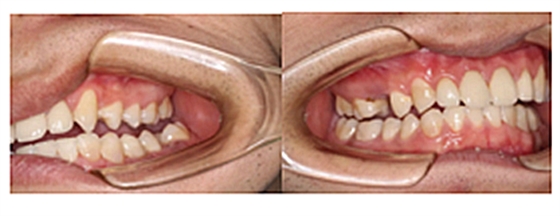

我們的主人今年才25歲,可卻從很小的時(shí)候就嗜好喝可樂等碳酸飲料,幾年下來,讓我們兄弟姐妹們整天浸在碳酸里受這蝕骨之痛,原本皎潔的外貌如今早己經(jīng)是腐蝕不堪、丑陋無(wú)比,更有甚者,一些兄弟姐妹們已經(jīng)病入膏肓,被病痛折磨奄奄一息。

再來看看曾經(jīng)的我們

經(jīng)歷了如此長(zhǎng)久的治療,主人應(yīng)該也是吸取了教訓(xùn),或許以后會(huì)改了不良的生活習(xí)慣,而我們經(jīng)歷了這段涅槃之旅,雖然也煥然一新,重塑了容顏,卻也是歷經(jīng)辛苦,如果主人能好好待我們,其實(shí)這樣的痛苦本不需要經(jīng)歷。